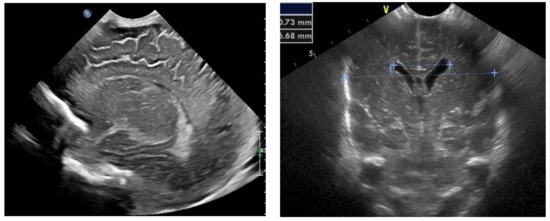

The results of the diagnostic MRI, performed between 21 and 24 weeks of gestation, were assessed (Figure 1 and Figure 2). During the test, the following parameters were evaluated: size and location of the spina bifida, presence and size of the hernia sack, size of the cerebral ventricles, structure of the posterior fossa, and severity of the Chiari malformation. Prenatal fetal NMR allowed to evaluate the development of the remaining fetal organs. Only fetuses with no other developmental defects were deemed eligible for the prenatal intervention. The NMR findings were compared to the perioperative imaging of the spinal split and hernia sack. After open fetal prenatal repair of spina bifida aperta, a follow-up ultrasound was performed at 2 weeks postoperatively, and repeated every 10–14 days. A follow-up fetal NMR was performed at 6–8 weeks postoperatively (Figure 1 and Figure 2).

Group I—12 (12.5%) patients with no hernia sack on diagnostic imaging and during surgical repair (Figure 1).

Figure 1. (A) Fetal NMR at 21 weeks of gestation. The arrow indicates the myeloschisis, with the area of contact between the split and the uterine wall. (B) Fetal NMR at 26 weeks of gestation (4 weeks after intrauterine myeloschisis repair); the arrow indicates the site after a three-layer reconstruction of spina bifida aperta.